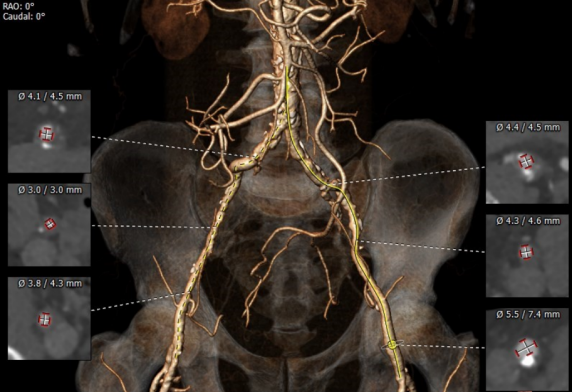

升主动脉CTA评估:三叶瓣,重度钙化,瓣环周长80.7mm,瓣环面积506.3mm²,左冠高度不高(11.3mm),右冠高度可(16.6mm),法式窦结构大,左室大小可,升主动脉未见明显扩张。瓣环角度可(41度)。

血管入路评估:双股动脉、左颈总动脉、左锁骨下动脉、右锁骨下动脉、右颈总动脉均不符合主路要求,升主动脉多发钙化,局部呈环形分布。

王焱教授、王斌教授及其团队与四川大学华西医院陈茂教授、冯沅教授团队对该病例进行了专题探讨,该病例为老年男性,主动脉瓣重度狭窄,术前心功能差,CT及心脏彩超提示三叶式主动脉瓣,瓣膜钙化重,瓣叶开放活动僵硬,高流速高压差重度主动脉瓣狭窄伴中度关闭不全,主动脉弓长度可,瓣环角度为41°,瓣口面积0.6cm2,外科手术高危,建议行TAVR。但患者外周动脉重度钙化伴狭窄,无法经股动脉、锁骨下动脉及颈动脉行TAVR,同时因升主动脉多发钙化(局部呈环形钙化),经升主动脉TAVR风险极高,且家属拒绝外科手术,综合评估考虑经腔静脉入路是可行的选择。经过团队严谨的评估及充分的讨论,决定经由腔静脉至腹主动脉建立手术入路,并采用启明Venus-A 26mm瓣膜实施TAVR。考虑患者LM70%狭窄,拟行TAVR同期LM PCI。